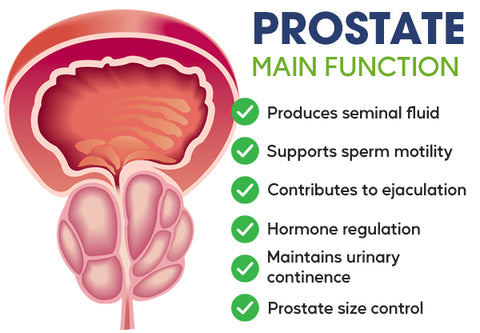

Changes in the prostate as you age

Because the prostate gland tends to grow larger with age, it may squeeze the urethra and cause problems in passing urine. Sometimes men in their 30s and 40s may begin to have these urinary symptoms and need medical attention. For others, symptoms aren't noticed until much later in life. An infection or a tumor can also make the prostate larger.

Lancetswell™ Saw Palmetto Prostate Health Supplement are meticulously crafted to provide comprehensive support for prostate health and alleviate the bothersome symptoms often associated with prostate issues.

Reducing Inflammation: Prostate problems are frequently linked to inflammation within the prostate gland. The capsules contain a unique blend of natural compounds renowned for their potent anti-inflammatory properties. By targeting and reducing inflammation in the prostate, these capsules help alleviate pain, discomfort, and swelling associated with prostate issues. Interferes with the production or activity of inflammatory mediators, such as cytokines and prostaglandins. By doing so, they help modulate the inflammatory response, resulting in a decrease in inflammation and swelling.

Enhancing Urinary Function: Frequent nighttime urination is a common symptom experienced by individuals with prostate issues. Lancetswell™ Prostate Health Capsules specifically target the smooth muscles and tissues surrounding the prostate and bladder. Through their action, these Capsules relax and strengthen these structures, leading to improved bladder control, reduced urinary urgency, and a healthier urinary flow. This ultimately results in fewer nighttime trips to the bathroom.